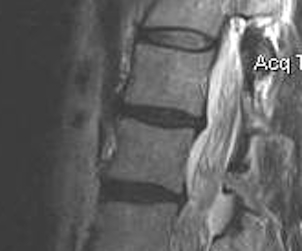

MRI

Disc

Normal disc / bright T2 signal

Degenerative disc / dark T2

Modic End Plate Changes

Classification of bone marrow changes in bone marrow adjacent to vertebral end plates

Type 1: High on T2 / Low on T1

Type 2: High on T2 / High on T1 (lipid changes)

Type 3: Low on T2 and T1 (sclerotic)